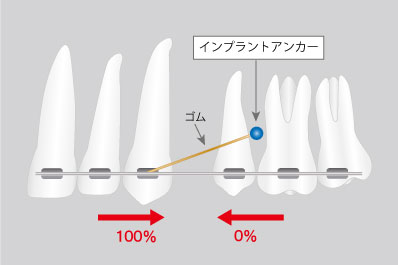

ワイヤー矯正で歯を動かす時には、奥歯を固定源としてゆっくりと他の歯を移動させて歯ならびを整えていきますが、引っ張られる側の奥歯が不安定で意図しない方向に歯が動いたり、歯をならべるのに時間がかかりすぎたりすることがありました。

矯正用アンカースクリューでは、内側に小さいネジを埋めます。顎の骨にしっかりと固定されたネジを固定源にすることで歯を動かす幅が広がり、効率的に歯の移動が可能になります。アンカースクリューを使用することで抜歯をせずに矯正ができる、治療期間が短くなるといった効果が期待できます。